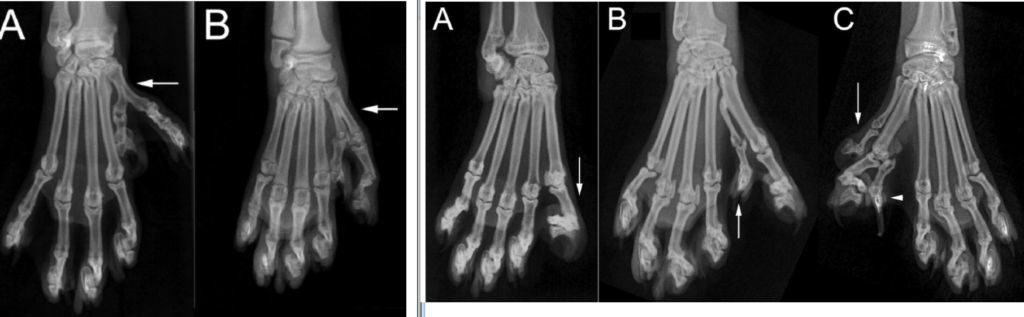

Буває двох видів:

- Преаксимальная – зайвий великий палець

- Постаксимальная – зайвий мізинець

Наявність додаткового великого пальця поширене сильніше, ніж поява додаткового мізинця. Лапа такого кота нагадує людську руку. Іноді їх називають — кіт в рукавицях.

Розташування пальців не передається від батьків.